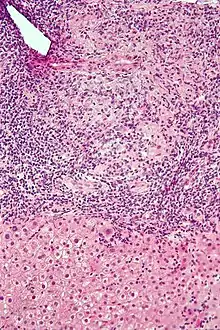

Micrograph of PBC showing bile duct inflammation and injury.

On microscopic examination of liver biopsy specimens, PBC is characterized by chronic, non-suppurative inflammation, which surrounds and destroys interlobular and septal bile ducts. These histopathologic findings in primary biliary cholangitis include the following:[34]

- Inflammation of the bile ducts, characterized by intraepithelial lymphocytes, and

- Periductal epithelioid granulomata.

- Proliferation of bile ductules

- Fibrosis (scarring)